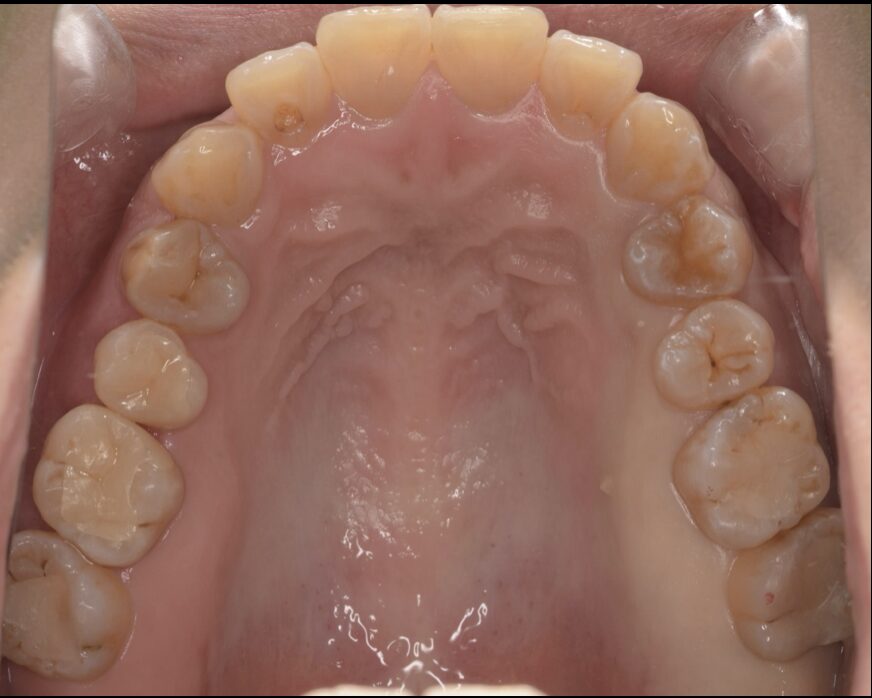

セラミックインレーにて治療した症例

Before

| 治療内容 | セラミックインレー(2本) |

| 治療期間・治療回数 | 2回 |

| 治療費用 | 143000円(税込) |

| 備考 | 40代 女性 |